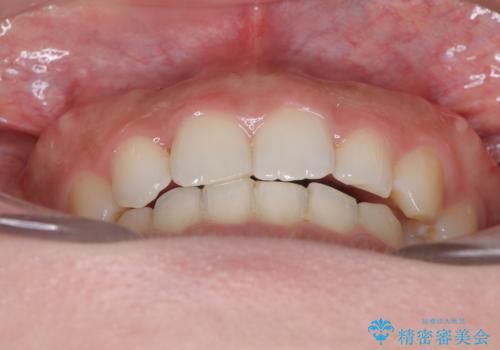

インビザラインで整える深い噛み合わせ

- 患者様は、ディープバイト(深い噛み合わせ)と、咬合平面の左下がりが気になるとのことでご来院されました。診断の結果、非抜歯で治療可能と判断し、透明なマウスピース型矯正装置「インビザライン」を用いる方針としました。治療では、歯列全体の調整を行いながら、咬合平面の水平化を重点的に進める計画を立案しました。2年間で計画的にマウスピースを交換し、左右のバランスと噛み合わせの改善を目指しました。

ディープバイトの矯正は、噛み合わせが深くなりがちなため、細心の注意を払いながら進める必要があります。本症例では、奥歯の高さを調整しつつ前歯の噛み合わせを浅くすることで、全体の咬合バランスを整えました。また、咬合平面の左下がりを修正する過程で、歯列に不均等な力がかからないよう、インビザラインのアタッチメント配置を最適化しました。患者様には装着時間を守っていただき、治療が計画通り進むよう協力をお願いしました。治療終了後には、リテーナーを装着して安定性を確保しました。